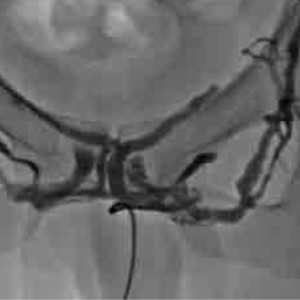

![Дорсальная флебография вен полового члена]()

Для того чтобы получить объективные данные о состоянии венозного оттока из полового члена, с возможностью одномоментной коррекции патологической утечки мы разработали технологию флебографии глубоких вен полового члена во время эрекции. Техника заключается во введении через ангиографический катетер без пункции кавернозных тел вазоактивного препарата (алпростадила или папаверина). После возникновения эрекции проводится пункция глубокой дорсальной вены пениса под УЗИ контролем.

Установив в просвет ангиографический катетер, мы вводим контрастное вещество в вену и наблюдаем за патологическими утечками. При выявлении утечки мы можем сразу выполнить её эмболизацию спиралью, чем устраняем проблему. Такой прицельный метод обладает максимальной эффективностью и безопасностью для пациента. Результат пациенты отмечают уже через неделю после вмешательства.